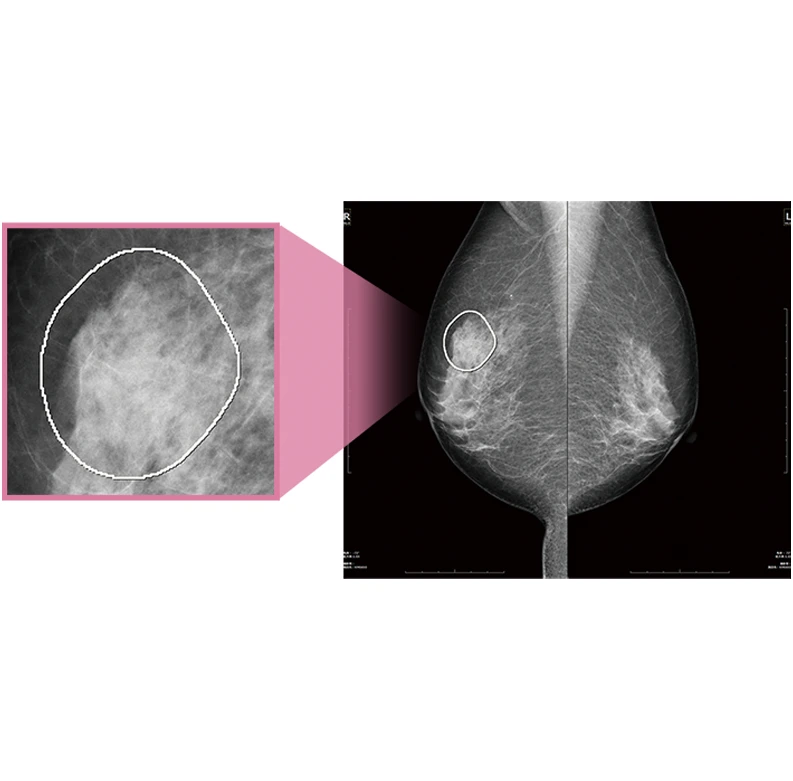

6. 乳がんの早期発見から治療まで Women’s Health

『FINO.VITA.GX typeMG』はマンモグラフィ診断に最適なワークフローを実現し、乳腺領域に特化した充実機能を搭載した専用ビューワーです。乳腺専用レポーティングシステムやマンモグラフィ診断支援CAD『MGCAD-i』もラインナップし、効率的な診断をサポートします。さらに乳房構成解析ソフトウェア『Breast Density Assessment(Bda)』は乳房構成を定量的に判定。ブレストアウェアネスの促進、そして、一人ひとりにとってよりよい乳がん検診を提案します。